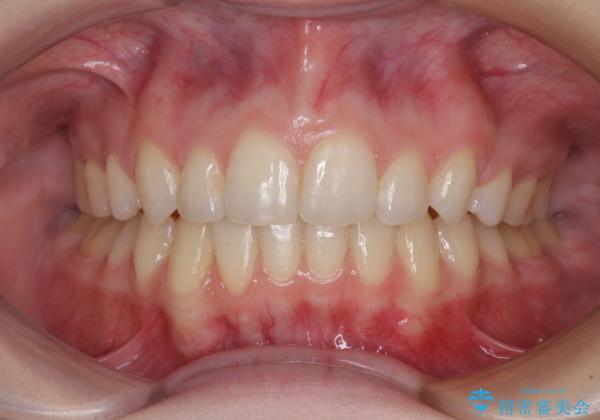

下顎の骨格的なズレが大きかったため、上下歯列のバランスが取れるか心配でしたが、上下ともに左右対称に近い歯列で治療を終えることができました。